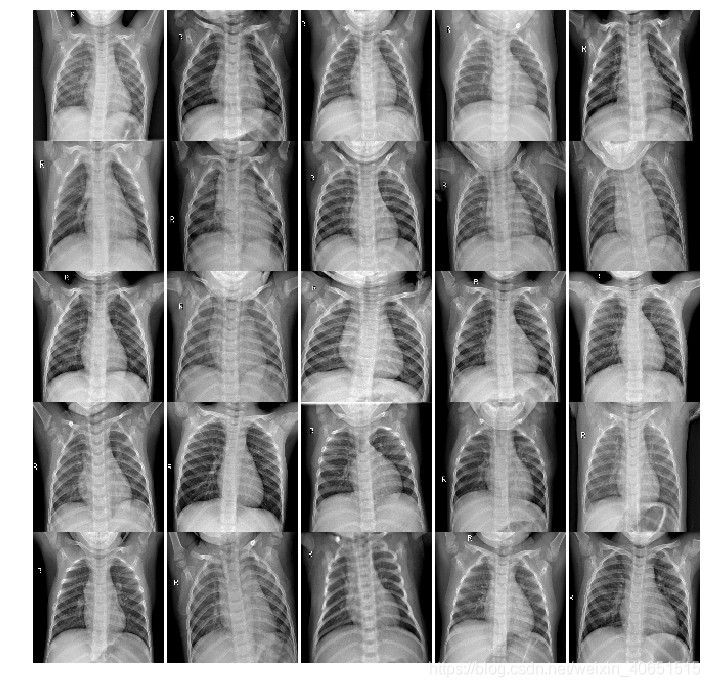

数据集样本展示:肺炎样本X-ray图像和正常X-ray肺部图像

正常肺部X-ray图像: